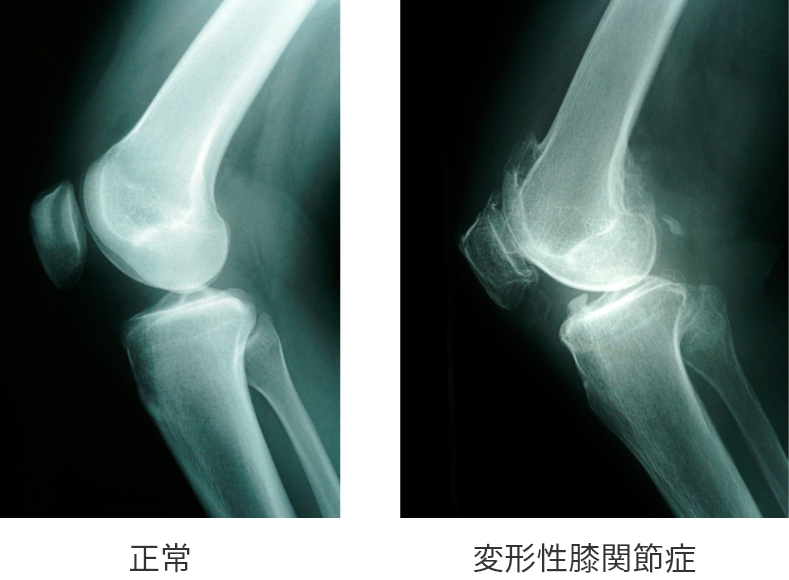

DISCRIPTION 変形性膝関節症とは

- 変形性膝関節症の病態

変形性膝関節症とは、膝関節の軟骨がすり減ることにより慢性炎症や変形が生じ、膝に痛みが生じる病気です。

この病気の原因には、膝の軟骨の表面が荒れてすり減り、それによって半月板が切れてしまうことが挙げられます。しかし反対に、先に半月板が切れてしまうことで膝にかかる衝撃を和らげるクッションの役割ができなくなり、結果として軟骨に障害が及ぶ場合もあります。

つまり、軟骨と半月板のどちらが先に痛むかは、人により異なります。